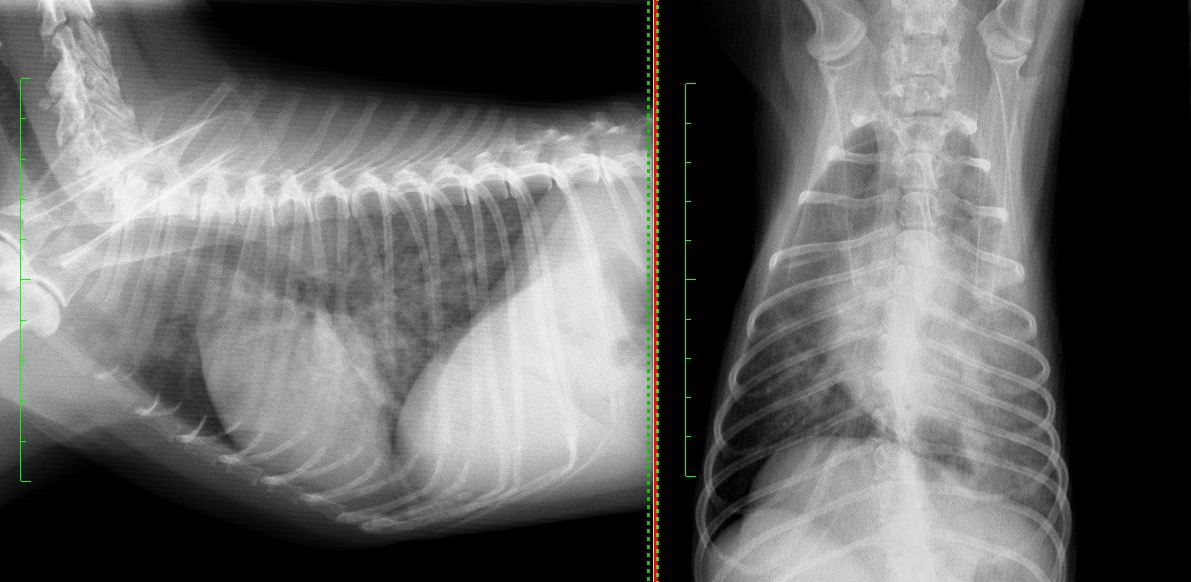

下に示すものがその時の胸部X線写真になります。 肺野が全体的に白くなり(不透過性の亢進)、その他検査と合わせ、肺炎の可能性が高いと診断し、すぐに入院下での治療を開始しました。